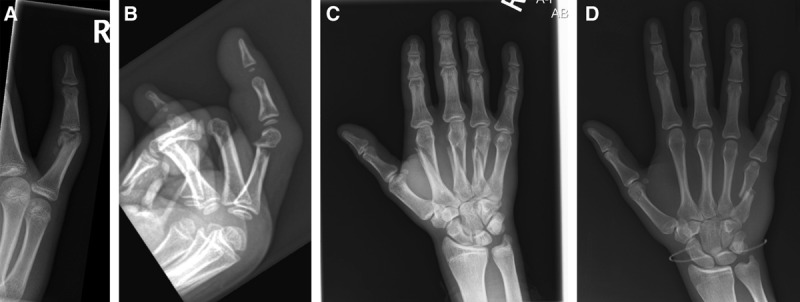

Fig. 2.

Example radiographs of common surgical fractures. A, Unicondylar proximal phalanx fracture. B, Proximal phalangeal neck fracture. C, Multiple oblique midshaft metacarpal fractures. D, Transverse midshaft metacarpal fracture.

For metacarpal fractures, two patterns were associated with an increased need for surgical intervention. First, 20.7% of midshaft fractures, either an oblique or transverse, required operative fixation (accounting for 16.5% of all operative cases). Second, 9.5% of fractures of the metacarpal base required surgical intervention (accounting for 11.3% of operative cases); these fractures most commonly involved the first metacarpal (Bennet’s or non-Bennet’s fracture at the base of first metacarpal) or the fifth metacarpal (baby Bennet’s fracture). Fractures of the neck of the metacarpal (ie, Boxer’s fractures) were the least likely to require surgery (1.3% required surgery, accounting for 1.7% of operative cases).